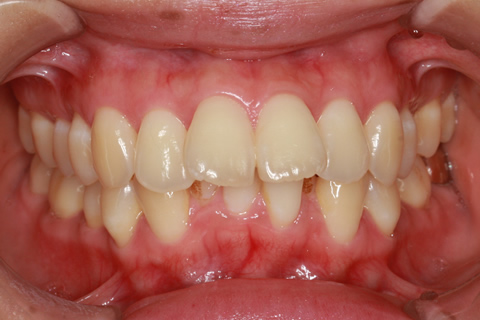

ハーフリンガル矯正3:上の歯のみ舌側矯正で治療(矯正期間24ヶ月)

治療前

治療中(開始直後)

治療中(開始半年後)

治療後

- 年齢・性別

- 25歳女性

- 治療期間

- 2年0ヶ月

- 抜歯

- 上下4番抜歯

- 治療費

- 110万円

- 治療内容

- 施術の副作用(リスク)

- 表側矯正と比較して、力学的な操作性が複雑なため、ボーイングエフェクトを起こしやすい。